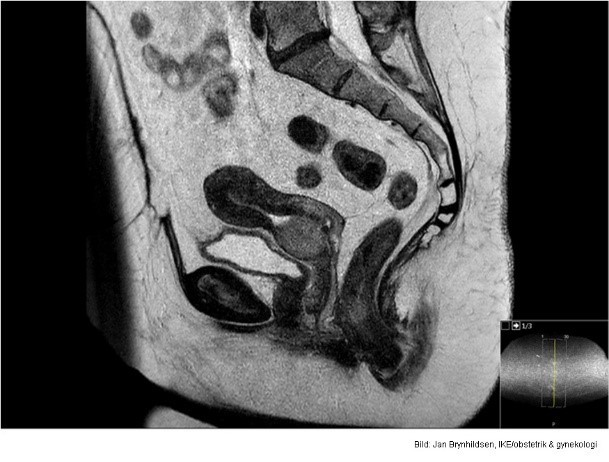

Vad visar bilden?

Invasivt växande skivepitelcancer.